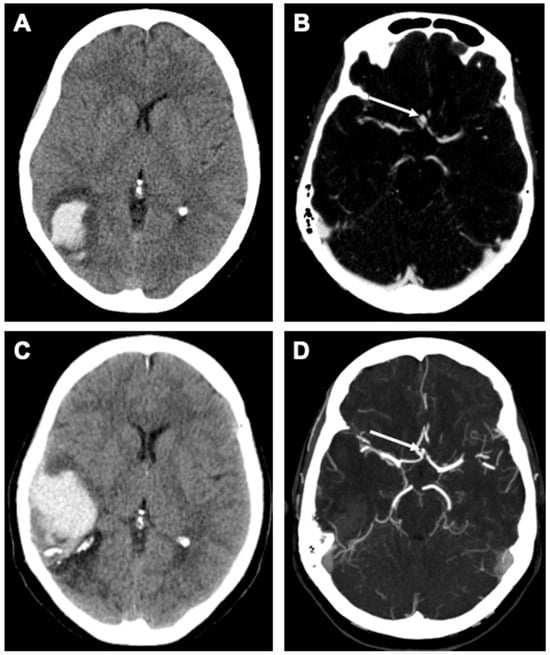

Case Description

2.5. Outcome and Follow-Up

| 56 y/o | ACom | 3 × 4 mm (diagnosis) 2 × 2.5 mm (FU) | 9 years |